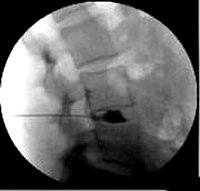

Дискография позвоночника. Рентгенологическое исследование межпозвонкового диска с использованием контрастирования. Он используется для выяснения причин боли неясного генеза, оценки состояния дисков при множественных поражениях, проведения дифференциальной диагностики между различными патологиями дисков, определения показаний к хирургическому вмешательству, планирования операции. Он включает местное введение контрастного вещества в область диска с последующей рентгенографией в двух проекциях. По показаниям проведены функциональные испытания. В настоящее время спинальная дискография редко назначается из-за появления альтернативных неинвазивных методов исследования (МРТ).

Дискография назначается для выявления источника боли, которую невозможно обнаружить с помощью других методов обследования. Исследование используется для изучения состояния дисков при их многоуровневом поражении, для дифференциальной диагностики рецидива межпозвонковой грыжи от рубцовых изменений, для определения причины болей после стабилизирующих операций на позвоночнике, для определения целесообразности операции и разработка операционного плана.

В современной неврологии дискография шейки матки и поясницы рассматривается как метод скрининга для диагностики патологии межпозвонкового диска. С другой стороны, дискография грудного отдела позвоночника показана только в тех случаях, когда другими способами невозможно получить необходимую информацию о состоянии диска. При возможности МРТ позвоночника показания дискографии значительно снижены и исследование дисков грудного отдела не используется. Обследование абсолютно противопоказано, если у пациента имеется неврологический дефицит, признаки активного инфекционного процесса, сдавление спинного мозга, а также кожные поражения в месте введения иглы. Стеноз позвоночника на уровне исследования, миелопатия и коагулопатия являются относительными противопоказаниями.